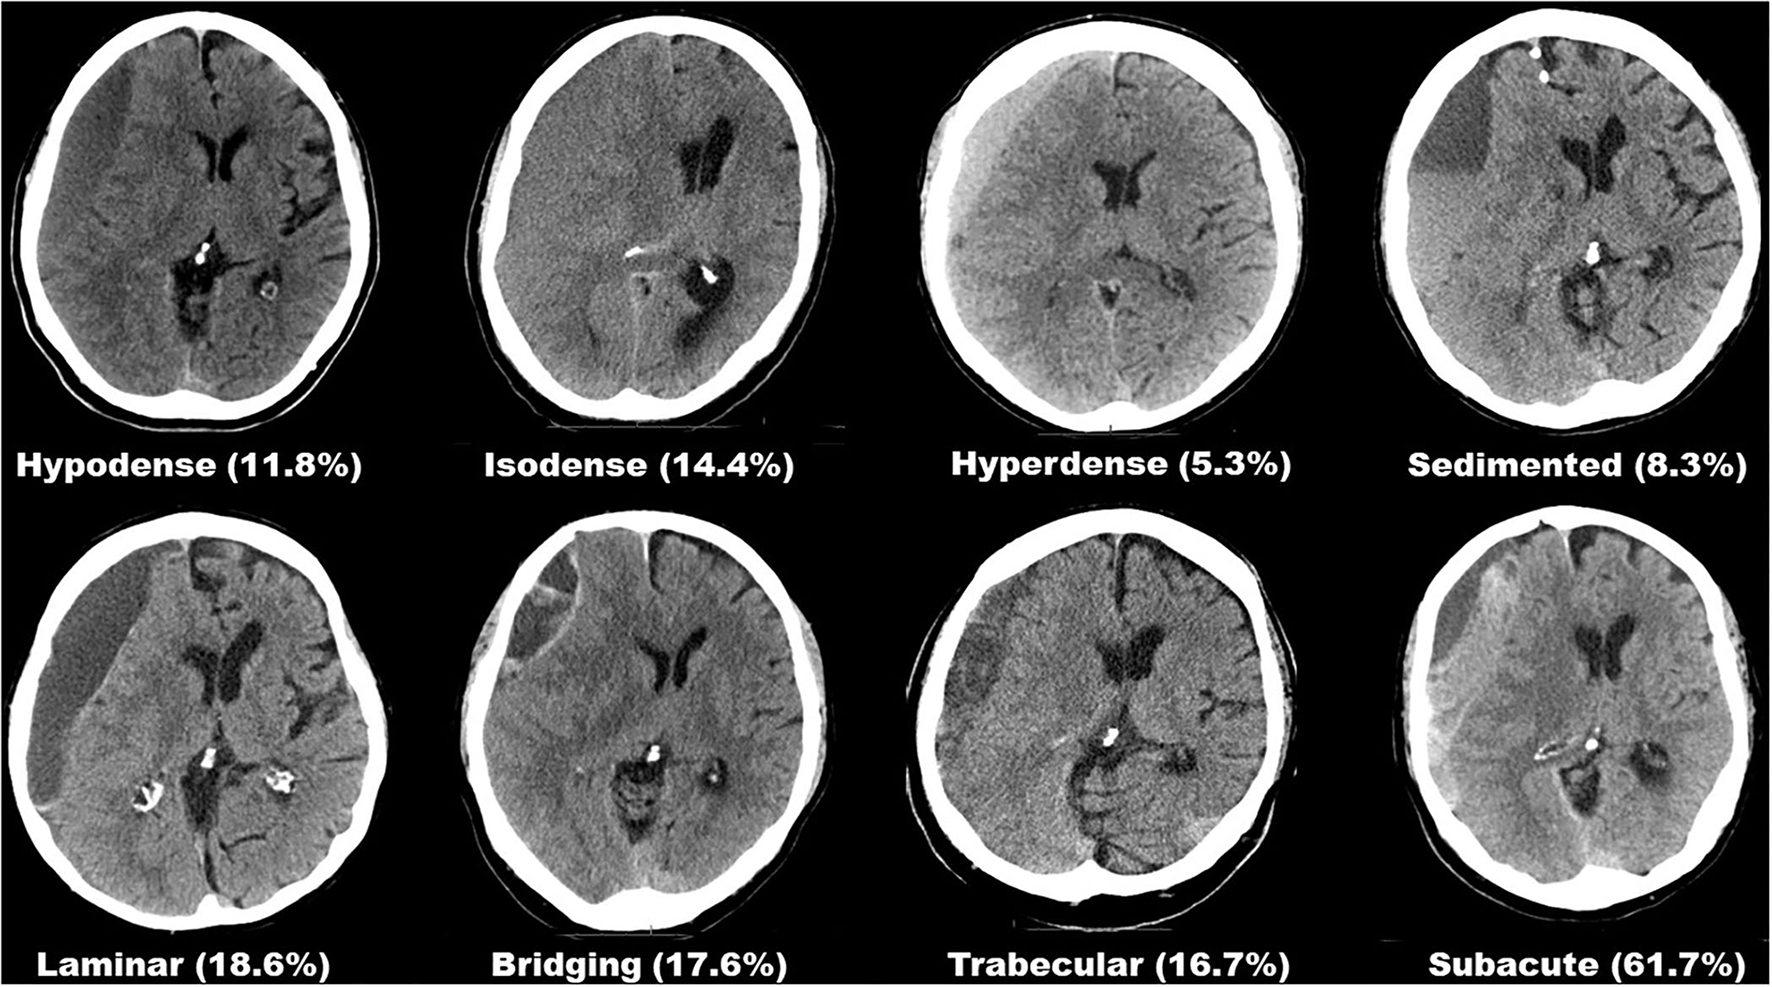

Preoperative hematoma dimensions were measured in axial CT images as: length along the longest axis (mm), width at its widest (mm), and volume (ml) were software assisted reconstructed (Brainlab, Munich, Germany). The presence of midline shift and its extension (mm) was noted. Two independent assessors (HH and MV), blinded to the outcome, classified each hematoma according to its structural appearance in CT imaging into one of eight subtypes, as described previously (6). All eight hematoma subtypes are depicted in Figure 1. Postoperative depressed brain volume (ml) was also software-assisted measured out (Brainlab, Munich, Germany) in post-operative imaging (13). Depressed brain volume includes all supratentorial intracranial volume not filled with re-expanded brain, e.g., residual hematoma, rinsing fluid, and air.

Figure 1

Overview of all eight hematoma subtypes based on internal architecture as seen in CT imaging and their respective rates of suspected seizure.